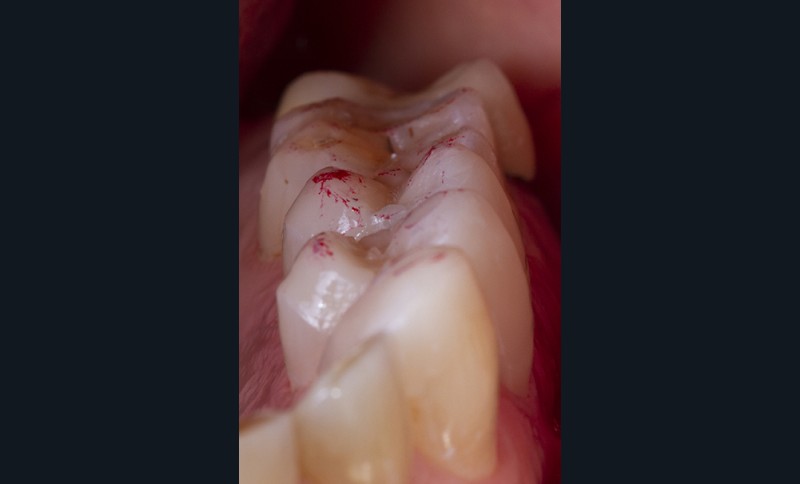

Enfin, une analyse attentive des courbes d’occlusion est menée, notamment dans les cas d’édentements non compensés ou lorsque des restaurations en céramique sont déjà présentes [12] (fig. 1). En effet, la présence de ces dernières peut entraîner une usure différenciée de la dent naturelle antagoniste.

Ainsi, les usures engendrent, dans la majorité des cas, des perturbations au niveau des courbes d’occlusion, lesquelles devront être corrigées lors de la réalisation du wax-up [13].